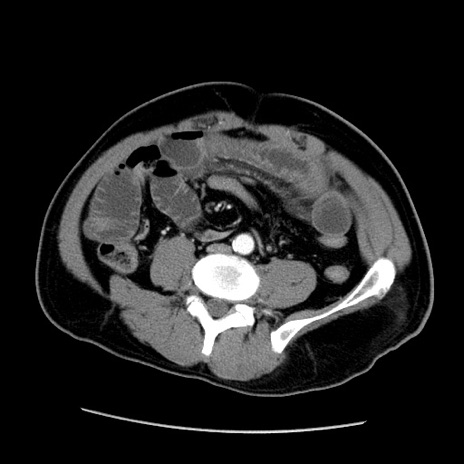

症例22(横断像)

【症例】50歳代男性

【主訴】腹痛

【現病歴】AVMからの被殻出血のため回復期リハ病棟入院中。 本日午後3時頃急に下腹部痛が出現した。

【既往歴】AVM、被殻出血、虫垂炎、高血圧

【身体所見】意識晴明、左半身不全麻痺、会話の理解は良好、36.5°C、腹部:膨隆、全体に板状硬、下腹部正中に圧痛点あり、反跳痛-、筋性防御不明、右下腹部にope scar

【データ】WBC 9400、CRP 0.06